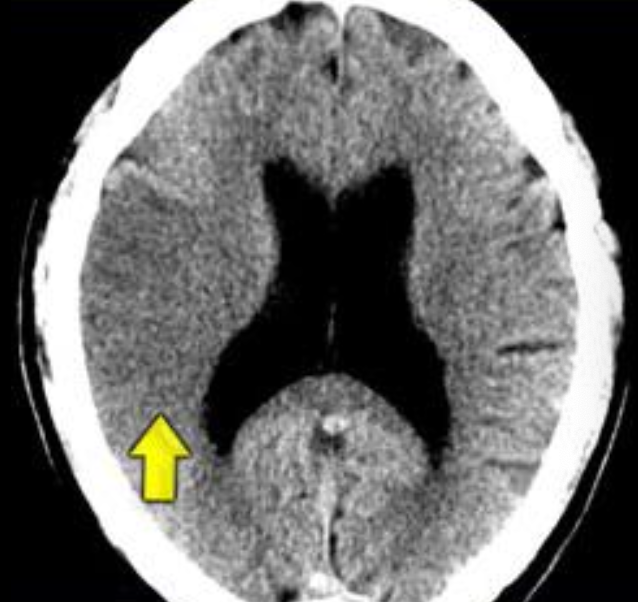

1

Q

A

EVC isquémico

Fase hiperaguda